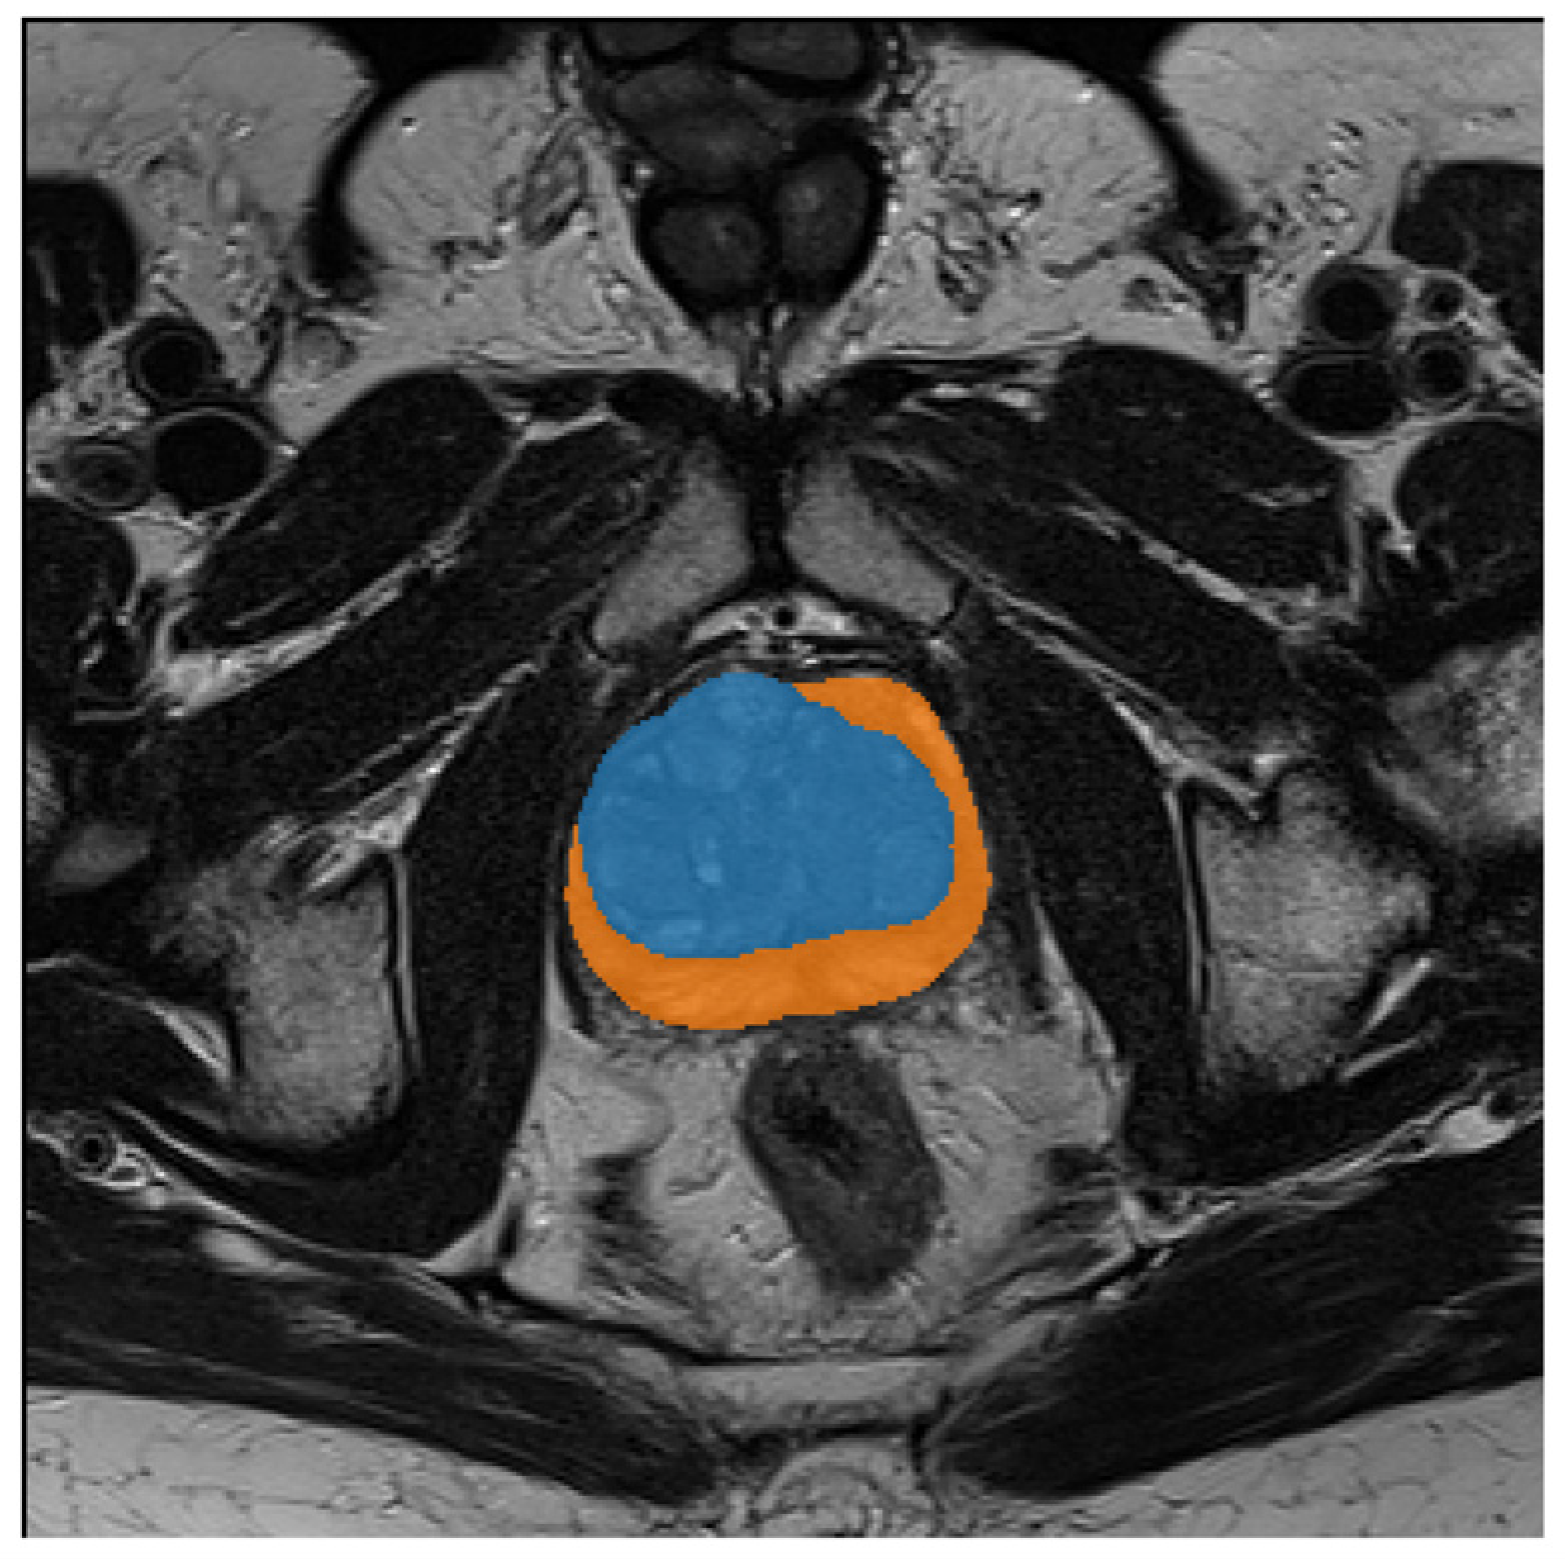

From the initial dataset, 326 MRI images of prostates collected from 41 patients were selected, in which the images were free of imaging artefacts and segmentation and visualization of the lesions were possible despite the rigorous PIRADS protocol. The number of projections per patient, which include the prostate, varies between 4 and 11 scans. Figure 1 shows the histogram of the number of MRI scans per patient. Each scan is supported with a manual annotation marking the inner (blue) and outer (orange) regions of the prostate, as depicted in Figure 2. For one patient, the outer prostate region was not annotated because this anatomical structure was absent. The mean age was 64.6 ± 9.8 with median age 65. The mean level of PSA in the cohort was 6.1 ± 3.9 with the median at 5.14. More detailed information on the cohort is given in Appendix A.

Figure 2. Visualization of the manual annotations prepared for each prostate MRI scan. The inner regions are depicted in blue, while orange shows the outer prostate region.